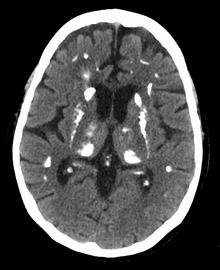

| Thyroid and parathyroid. | |